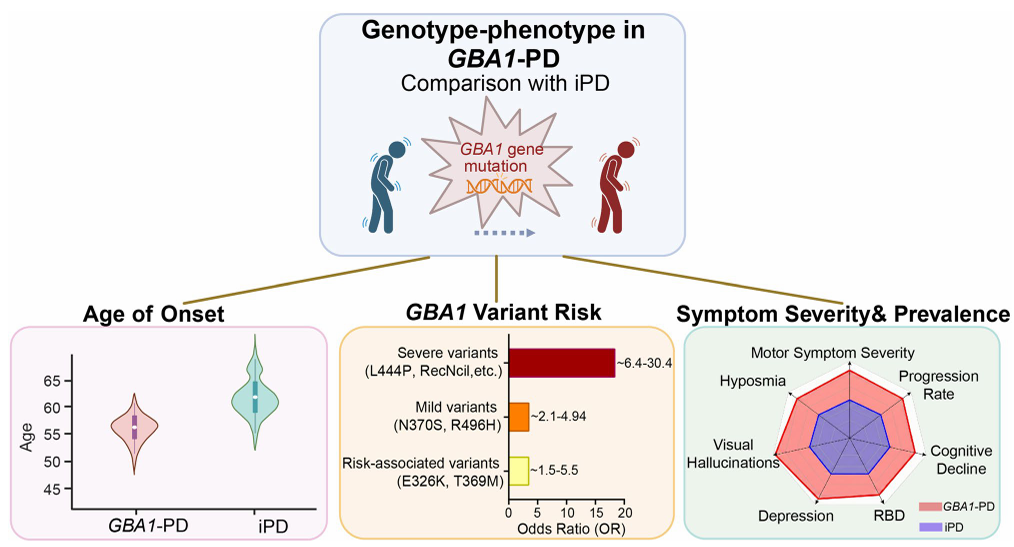

7. (MOL NEURODEGENER,IF:14.9) GBA1相关帕金森病的多组学见解:基因组学、转录组学、蛋白质组学和脂质组学的相互作用

图. GBA1相关帕金森病的独特临床表型

7. (MOL NEURODEGENER,IF:14.9) GBA1相关帕金森病的多组学见解:基因组学、转录组学、蛋白质组学和脂质组学的相互作用

图. GBA1相关帕金森病的独特临床表型